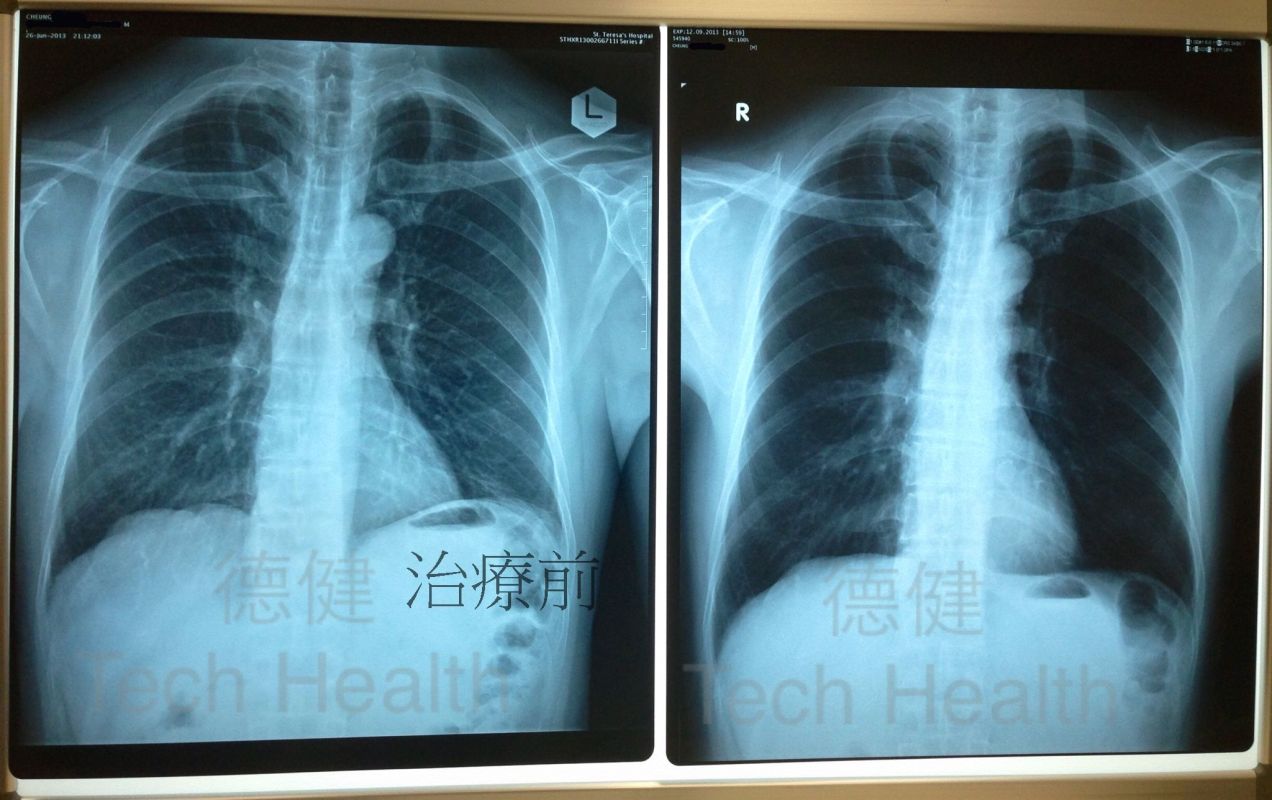

初診時間—2013/07/11症候:

1.從X光片檢查發現患者肺部纖維化,引致患者呼吸困難,上落樓梯氣喘更甚,全身乏力,雙腳水腫,兼有痛症,早泳習慣亦因而停止。

患者經過45次經穴激活系統療法的組合治療後,所有不適症狀均已消除,從覆檢的X光片中,可見肺部組織纖維化部份有95%以上回復正常,而患者亦已回復正常生活,且生活質素良好。